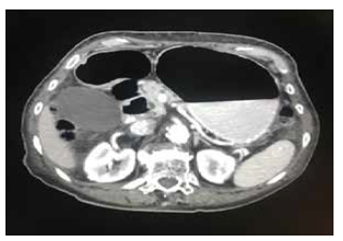

Por persistencia del cuadro clínico, se solicitó TC abdominal con contraste, en la que se apreció un íleo parcialmente obstructivo, hernia diafragmática derecha, dilatación esofágica indicativa de acalasia y derrame pleural y atelectasias en ambas bases pulmonares (figura 1 y 2.

Figura 1. TC abdominal con contraste: distensión gástrica, y de la primera y la segunda porciones del duodeno.

Figura 2. TC abdominal con contraste: importante distensión de asas intestinales sin divertículos evidentes a este nivel.